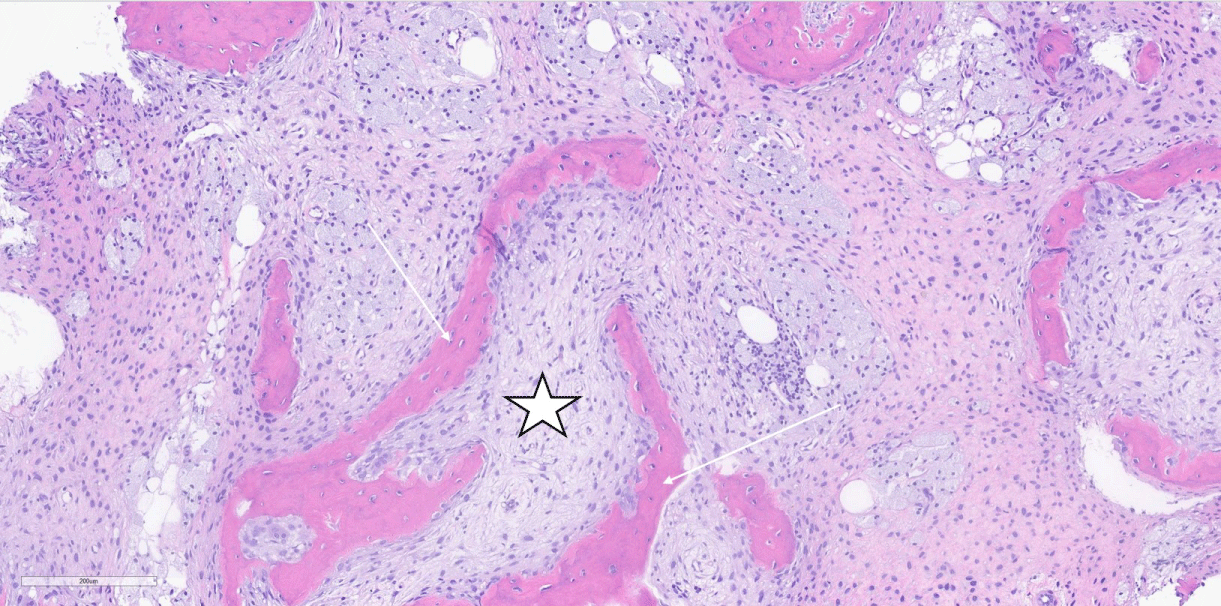

Figure 2: H&E, 10X magnification of breast core biopsy showing both a normal duct (star) adjacent to grade 3 invasive ductal carcinoma (arrows). View Figure 2

A 55-year-old woman presented to our tertiary care facility referred from an outside institution after a 3 cm mass in her left breast was identified (Figure 1). The mass was biopsied, and she was subsequently diagnosed with a high grade invasive ductal carcinoma (IDC) (Figure 2). The cancer was negative for estrogen receptor, progesterone receptor and Her2. Additionally, the proliferative rate as assessed by Ki-67 was 85 percent. An axillary lymph node was suspicious by imaging, but not biopsied. A nuclear medicine bone scan with a Tc-99 m radiotracer was used to stage her cancer (Figure 3). The imaging showed increased radiotracer uptake in the right proximal femur and right distal tibia suggestive of metastases and therefore, the patient was considered to have stage IV metastatic breast carcinoma. However, radiographs of the right femur and tibia showed stable lesions without aggressive cortical involvement and a ground glass appearance suggestive of fibrous dysplasia (Figure 4A and 4B). A subsequent biopsy of the proximal femur lesion showed atypical fibrous tissue with S-shaped woven bone trabeculae that tested negative for MDM2 amplification, essentially ruling out low grade osteosarcoma which can sometimes histologically mimic FD [11] and confirming the imaging impression of fibrous dysplasia (Figure 5). Additional genetic testing showed that the fibrous dysplasia was caused by a somatic mutation on codon 201 of the GNAS gene, substituting cytosine in CGT for thymine (TGT). As the fibrous dysplasia was found incidentally as part of the patient’s metastatic work up and was generally asymptomatic, it was clinically followed. Her triple negative breast cancer responded to preoperative chemotherapy, and a subsequent left breast segmental mastectomy showed only treatment related changes and no residual disease. The sentinel lymph nodes were negative for metastatic carcinoma. The breast specimen was evaluated by molecular sequence analysis which revealed no mutation in exon 8 or 9 of the GNAS gene. The patient is currently well with stable polyostotic fibrous dysplasia and without residual carcinoma.